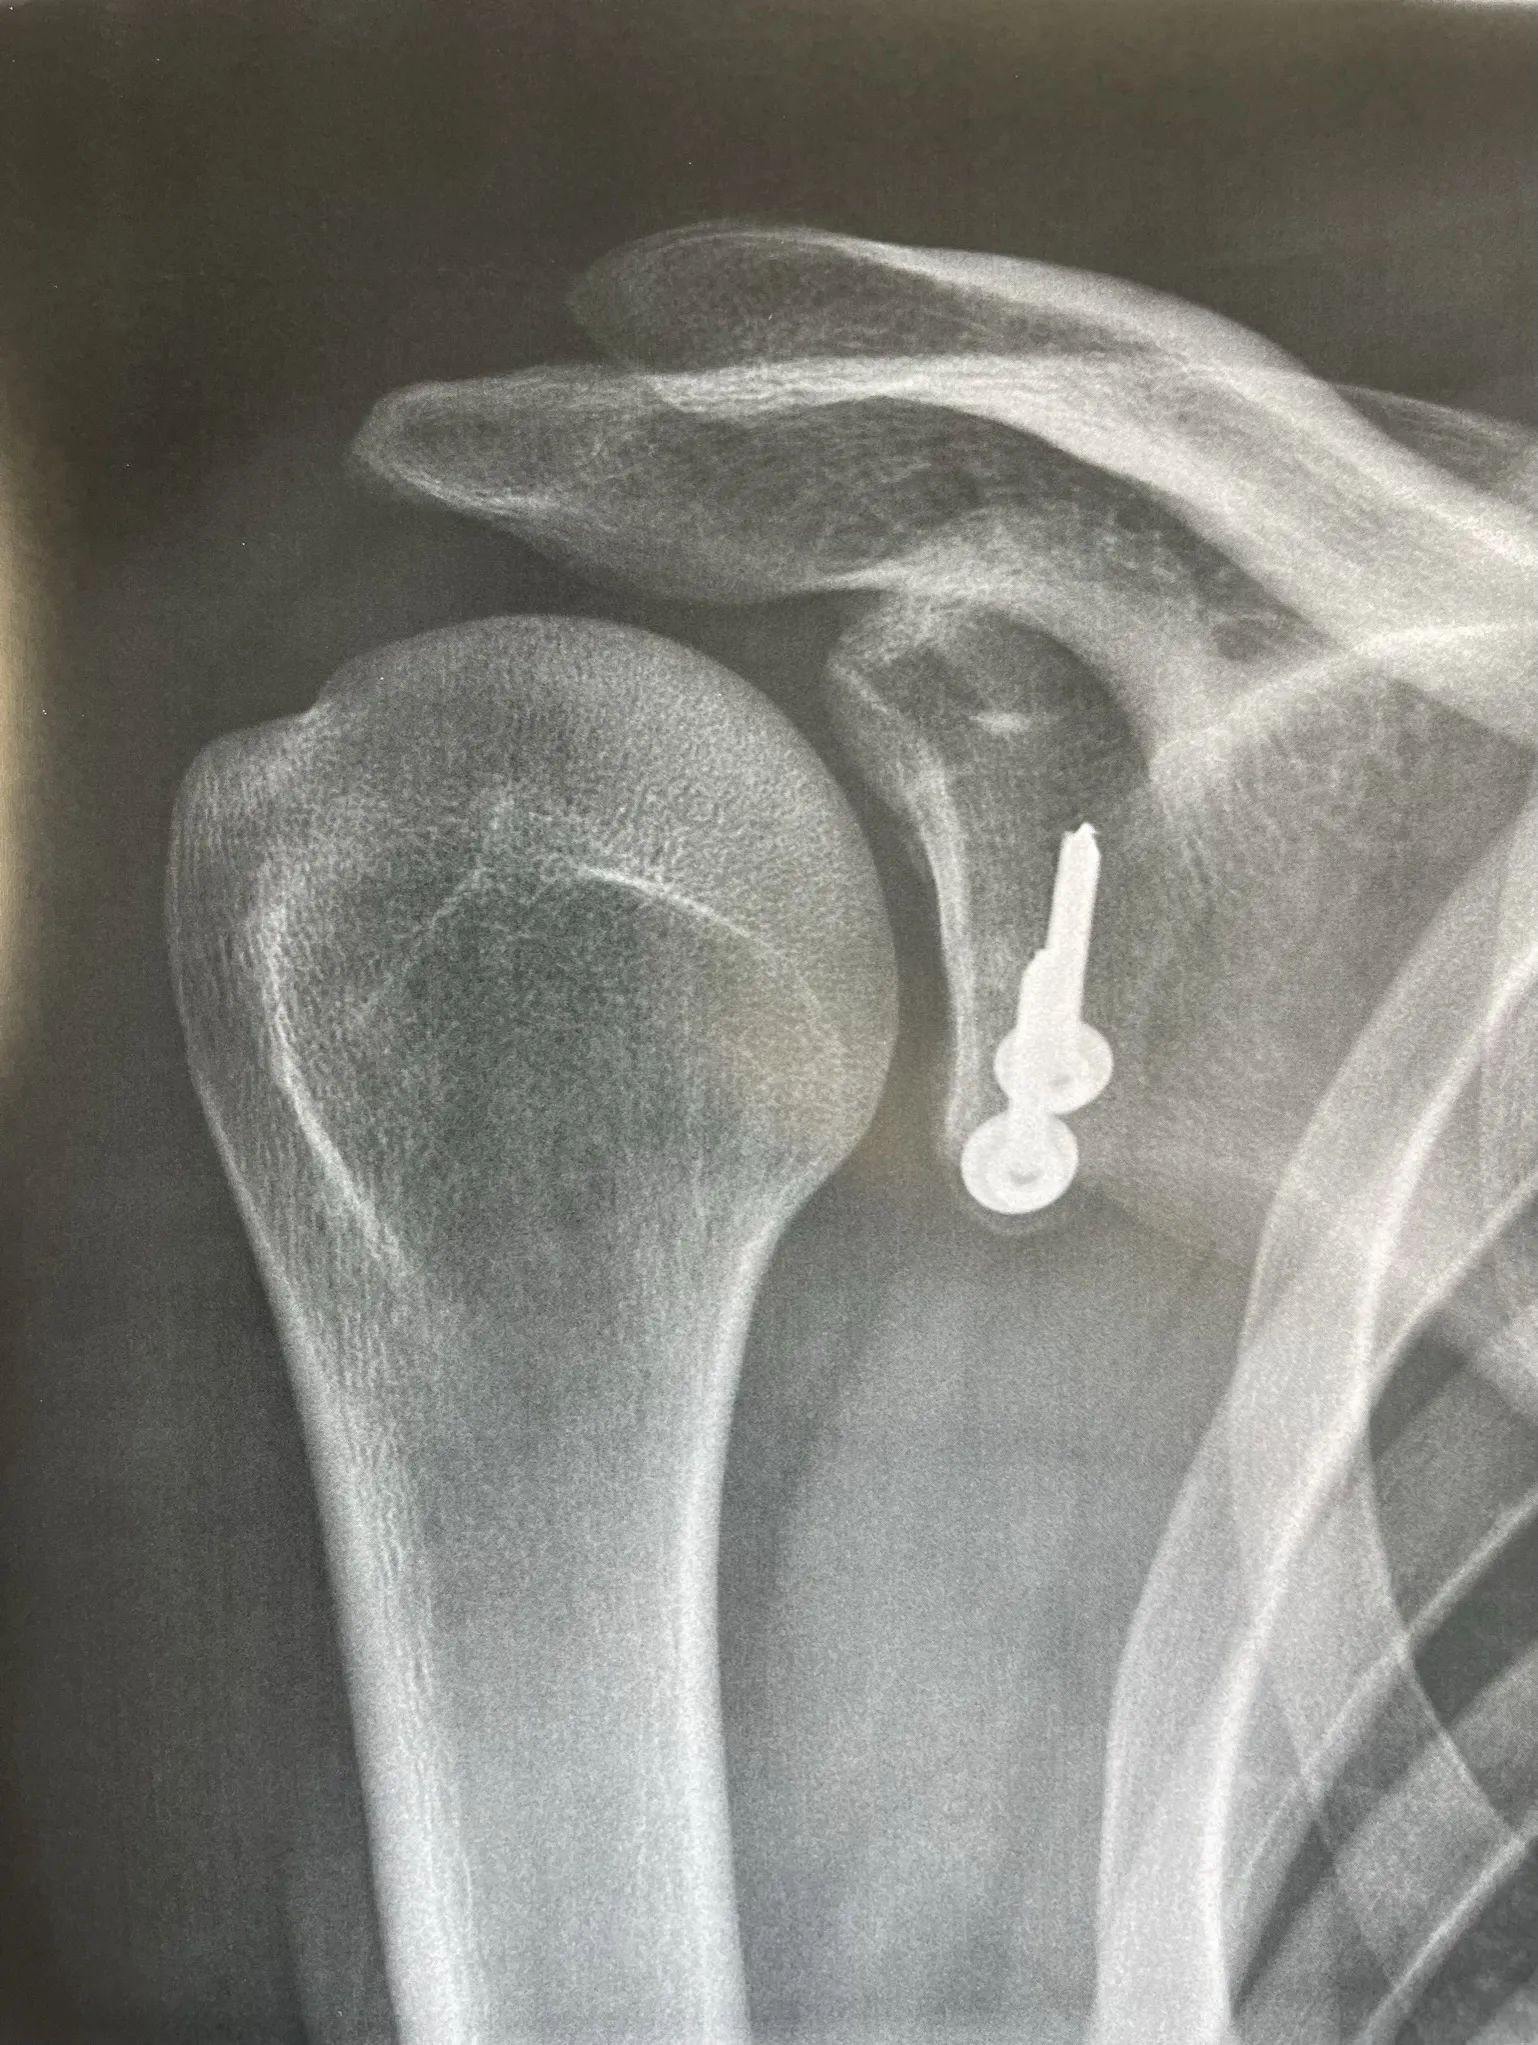

La butée coracoïdienne (Latarjet) — Mini-open avec fixation par endobuttons

Pour qui ? Perte osseuse glénoïdienne, récidives multiples, sport de contact ou d'armé-contré, score ISIS > 3.

Comment ? Un fragment osseux — la coracoïde — est détaché et transféré sur le bord antérieur de la glène par une incision mini-invasive (mini-open) de quelques centimètres. La fixation est assurée par un système d'endobuttons reliés par des fils à haute résistance, sans vis métallique.

Cette technique offre un triple effet stabilisateur : osseux (comblement de la perte osseuse glénoïdienne), ligamentaire (le ligament coraco-huméral retend le plan antérieur) et musculaire (le muscle conjoint s'oppose activement au déplacement antérieur de la tête humérale).

La fixation par endobuttons présente des avantages par rapport aux vis : pas de matériel rigide saillant, contraintes mécaniques mieux réparties sur la greffe, et pas de risque de fracture de vis.

Résultat : taux de récidive inférieur à 5%. Reprise sport de contact à 6 mois après consolidation radiologique confirmée.

Dans certains cas on peut être amené à proposer une fixation de la butée par une technique classique avec des vis. Cette chirurgie peut être également réalisée sous arthroscopie.

- Contrôle : radiographie en salle de réveil avant remontée en chambre